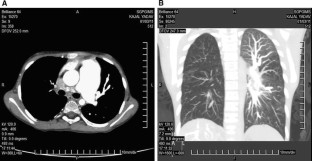

Takayasu’s Arteritis Mimicking Unilateral Pulmonary Artery Agenesis in a Child With Severe Pulmonary Hypertension and Right Heart Failure: A Diagnostic Dilemma

Affliction of the pulmonary arteries in Takayasu’s arteritis is uncommon. Moreover the incidence of pulmonary artery involvement in this condition is often underestimated because of asymptomatic nature in most patients. Severe involvement may however present with pulmonary artery hypertension and hemoptysis, which may prove to be fatal. This case report describes a 9-year-old girl with severe pulmonary hypertension and right heart failure secondary to total occlusion of the right pulmonary artery. Detailed clinical examination and computed tomography (CT) angiography confirmed this diagnosis.

Fig. 1